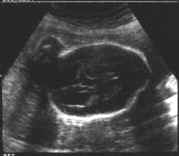

Coupes sagittales : parcourant tout le rachis (cliché gauche).

Coupes transversales : vertèbre par vertèbre (cliché droit).

- Sur une coupe sagittale stricte : corps vertébraux, canal rachidien (deux fines lignes parallèles) suivi jusqu’au cône terminal (effilé) et intégrité du revêtement cutané.

- Sur une coupe para-sagittale : corps vertébraux et lames latérales.

de dedans en dehors, corps vertébraux, canal rachidien, lames latérales, revêtement cutané.

Coupes frontales : Deux lignes parallèles discontinues régulièrement, correspondant aux lames latérales, au milieu le canal rachidien.

Existence d’un renflement lombaire précédent l’effilement terminal sacré.